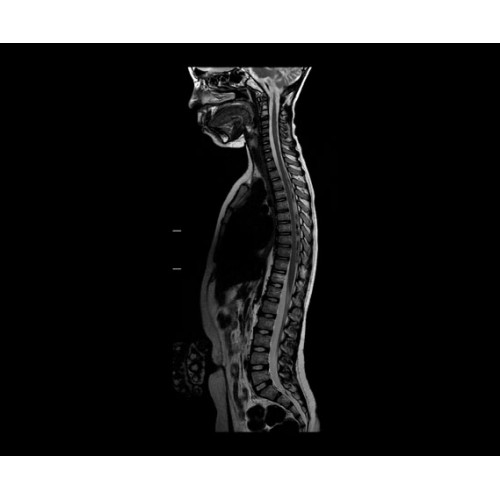

• NeuroWorks — универсальное решение для визуализации анатомии головного мозга, позвоночника, сосудов и периферических нервов с четкой дифференциацией тканей.

• Digital Surround Technology (DST)— это новая технология объемной оцифровки данных, которая объединяет сигналы от каждого элемента катушки. Прекрасное соотношение сигнал/шум и чувствительность поверхностных катушек в сочетании с превосходной однородностью и высокой проникающей способностью встроенной радиочастотной катушки — все это позволяет создавать качественные изображения не только позвоночника, но и всего тела.

• 48-канальная катушка TDI для головы, входящая в базовую комплектацию SIGNA Architect, обеспечивает феноменальную производительность с учетом особенностей каждого пациента. Благодаря гибкому и универсальному дизайну, высокому соотношению сигнал/шум и передовым технологиям визуализации, таким как HyperWorks, учитываются потребности подавляющего большинства пациентов.